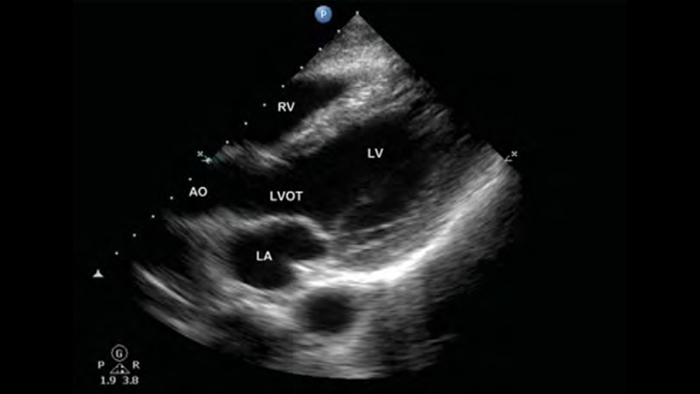

Ultrasonido cardíaco en el punto de atención prehospitalario: embolia pulmonar

• Rango extendido de frecuencias de operación de 4 a 1 MHz • 2D, Doppler a color, Modalidad M, XRES avanzado e imágenes armónicas multivariables • Imagenología de alta resolución para aplicaciones abdominales y cardíacas: optimizaciones de preajustes de imágenes cardíacas, gineco-obstétricas, pulmonares, abdominales y FAST.